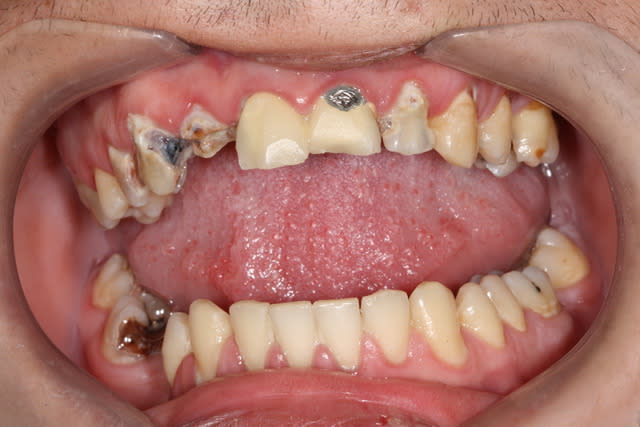

Ca y est, j'en tiens un !

Désolé pour la photo, l'appareil était là par hasard mais sans son flash.

Ce patient n'a pas vu de dentiste (ni de brosse à dent) depuis 40 ans. Le motif de consultation est une "légère gêne" à la mastication côté gauche.

Admirez le mouvement poétique et gracieux de la 47, figé en plein élan telle une danseuse.